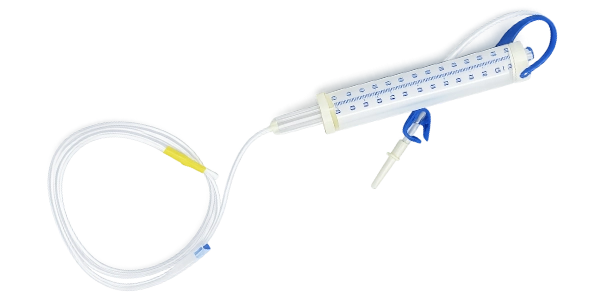

The Measured Volume IV Set (Burette Set) is specially engineered to ensure precise and controlled delivery of intravenous fluids and medications. Featuring a calibrated burette chamber, it allows accurate measurement of fluid volume, making it ideal for pediatric, neonatal, and critical care applications.

Contact Us NowIt is used to deliver precise and controlled amounts of intravenous fluids, especially in pediatric and critical care settings.

The burette chamber allows accurate measurement of fluid volume, helping prevent over-infusion and ensuring patient safety.

The Measured Volume IV Set is a disposable, single-use medical device intended for safe and hygienic use.